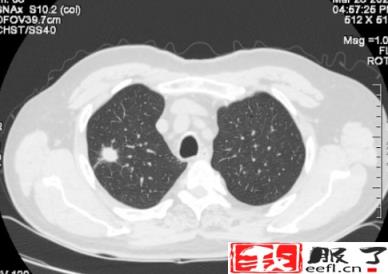

近年来,肺结节的发病率越来越高。我们经常可以看到或听到身边的亲友,体检时发现肺结节。造成这种情况的原因,一方面是现代人生活节奏快、工作压力大、生活习惯差、空气污染等,导致肺结节的发病率较以前有所增加。另一个方面是,过去在例行体检中,通过胸部X光片来确定肺部的状况。

但是X线对软组织的分辨率不是很高,小于一厘米的结节很难发现。现在,越来越多的人在体检时选择胸部CT检查。这样,随着医学影像诊断技术的进步,两到三毫米的肺结节也能被发现和检测到。因此,总的来说,肺结节的发现率越来越高。